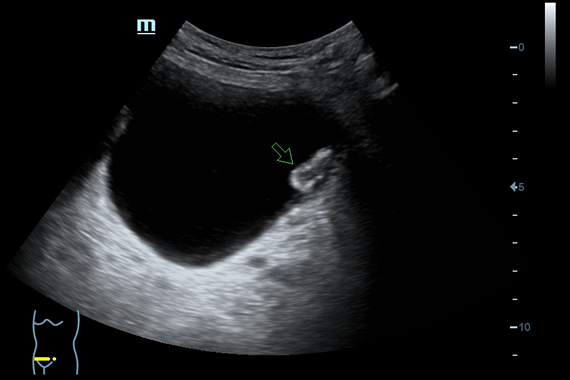

Система ультразвукового исследования Mindray DC-60 EXP X-INSIGHT является новейшей разработкой для проведения комплексных обследований на высшем уровне. Она обеспечивает решение самых сложных задач в таких областях, как кардиология, акушерство и гинекология, сосудистые заболевания, педиатрия и многие другие.

DC-60 EXP X-INSIGHT - это современный стационарный УЗИ-аппарат с функцией сенсорного управления и очищенной гармонической визуализацией, обеспечивающей лучшее контрастное разрешение и технологию 4D-визуализации. Он оснащен 21,5-дюймовым монитором, который может поворачиваться на 180 градусов, что удовлетворяет потребности врачей в качественной ультразвуковой диагностике.

• 4D - блок объемного сканирования в реальном времени

• iLive™ - режим построения объемного изображения с применением технологии виртуальной свето-теневой обработки с возможностью перемещения источника освещения (необходима опция Smart 3D или модуль 4D)

• iPage™ - мультисрезовое томографическое отображение с регулировкой толщины среза (необходим модуль 4D)